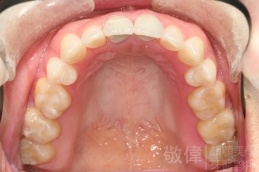

變臉矯正,原來戽斗妹跟大歪臉變成自信正妹

經由本院3D數影X光影像儀分析、與3D齒顎顏矯正技術,再配合口腔顎面正顎專科醫師施以正顎手術治療,雙方共同合作,使患者臉部外觀有很好的改善,大歪變小歪,產生了天南地北的大改變,她的人生也整個變得不一樣。

因為矯正與正顎手術的配合,使「戽斗妹」變成了「陽光正妹」,完全的改變了她的人生,在面對各種場合、與人交際都散發出自信微笑。所以,奉勸家長,如果小朋友有臉顎畸型的問題,應該考慮配合做這種簡單、安全、有效的正顎手術。

「3D齒顎顏矯正」,不止矯正您的牙齒,也會改變您的人生。「治療前」和「治療後」出社會的人生際遇一定會截然不同。